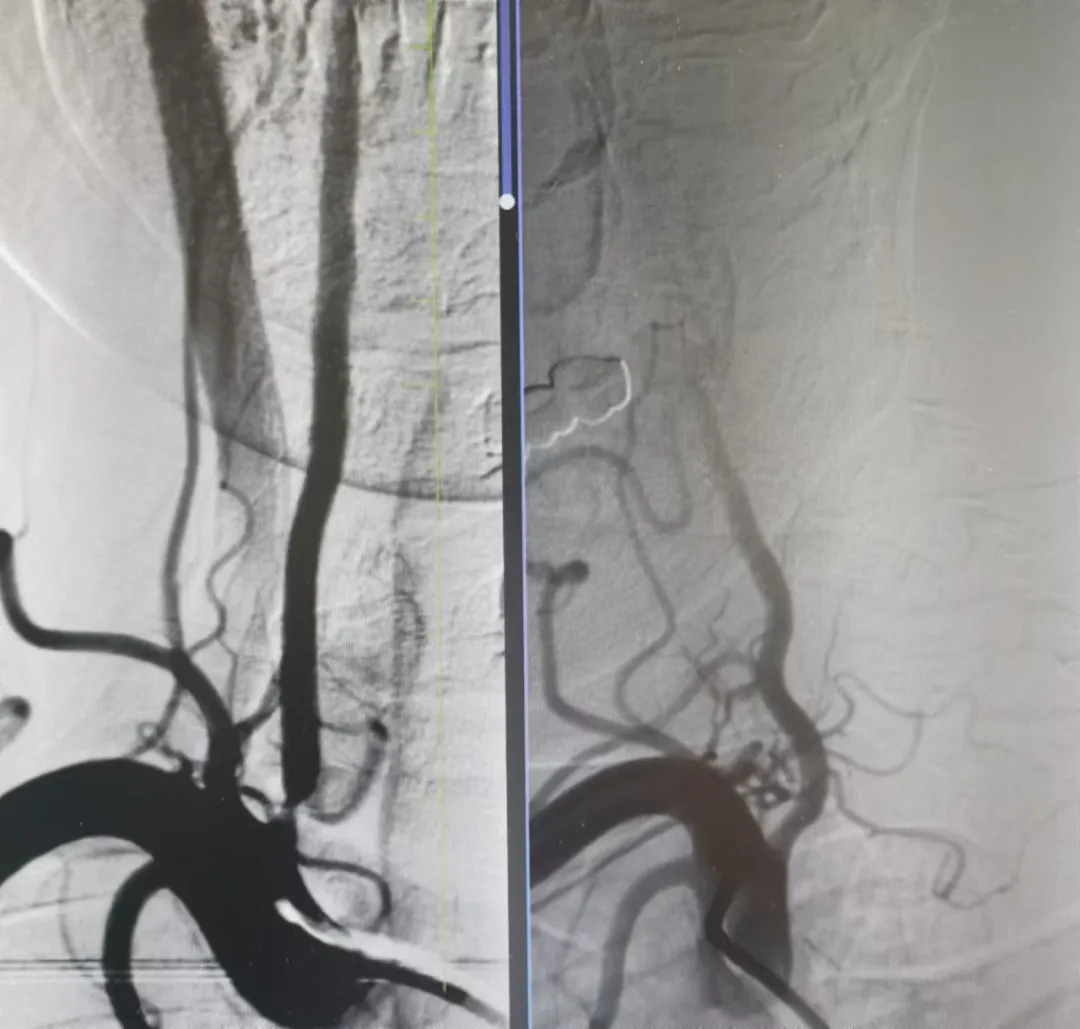

打通腦血管狹窄患者生命線(xiàn)丨國(guó)文醫(yī)院一天完成多例神經(jīng)介入手術(shù)

近日,國(guó)文醫(yī)院神經(jīng)介入科團(tuán)隊(duì)在丁金明主任和朱洪波副主任帶領(lǐng)下成功為兩例腦血管狹窄患者開(kāi)通幾近閉塞血管得到患者和家屬一致好評(píng)該項(xiàng)技術(shù)自開(kāi)展以來(lái)已為本地區(qū)眾多腦動(dòng)脈狹窄患者帶來(lái)福音 閱讀量:2914